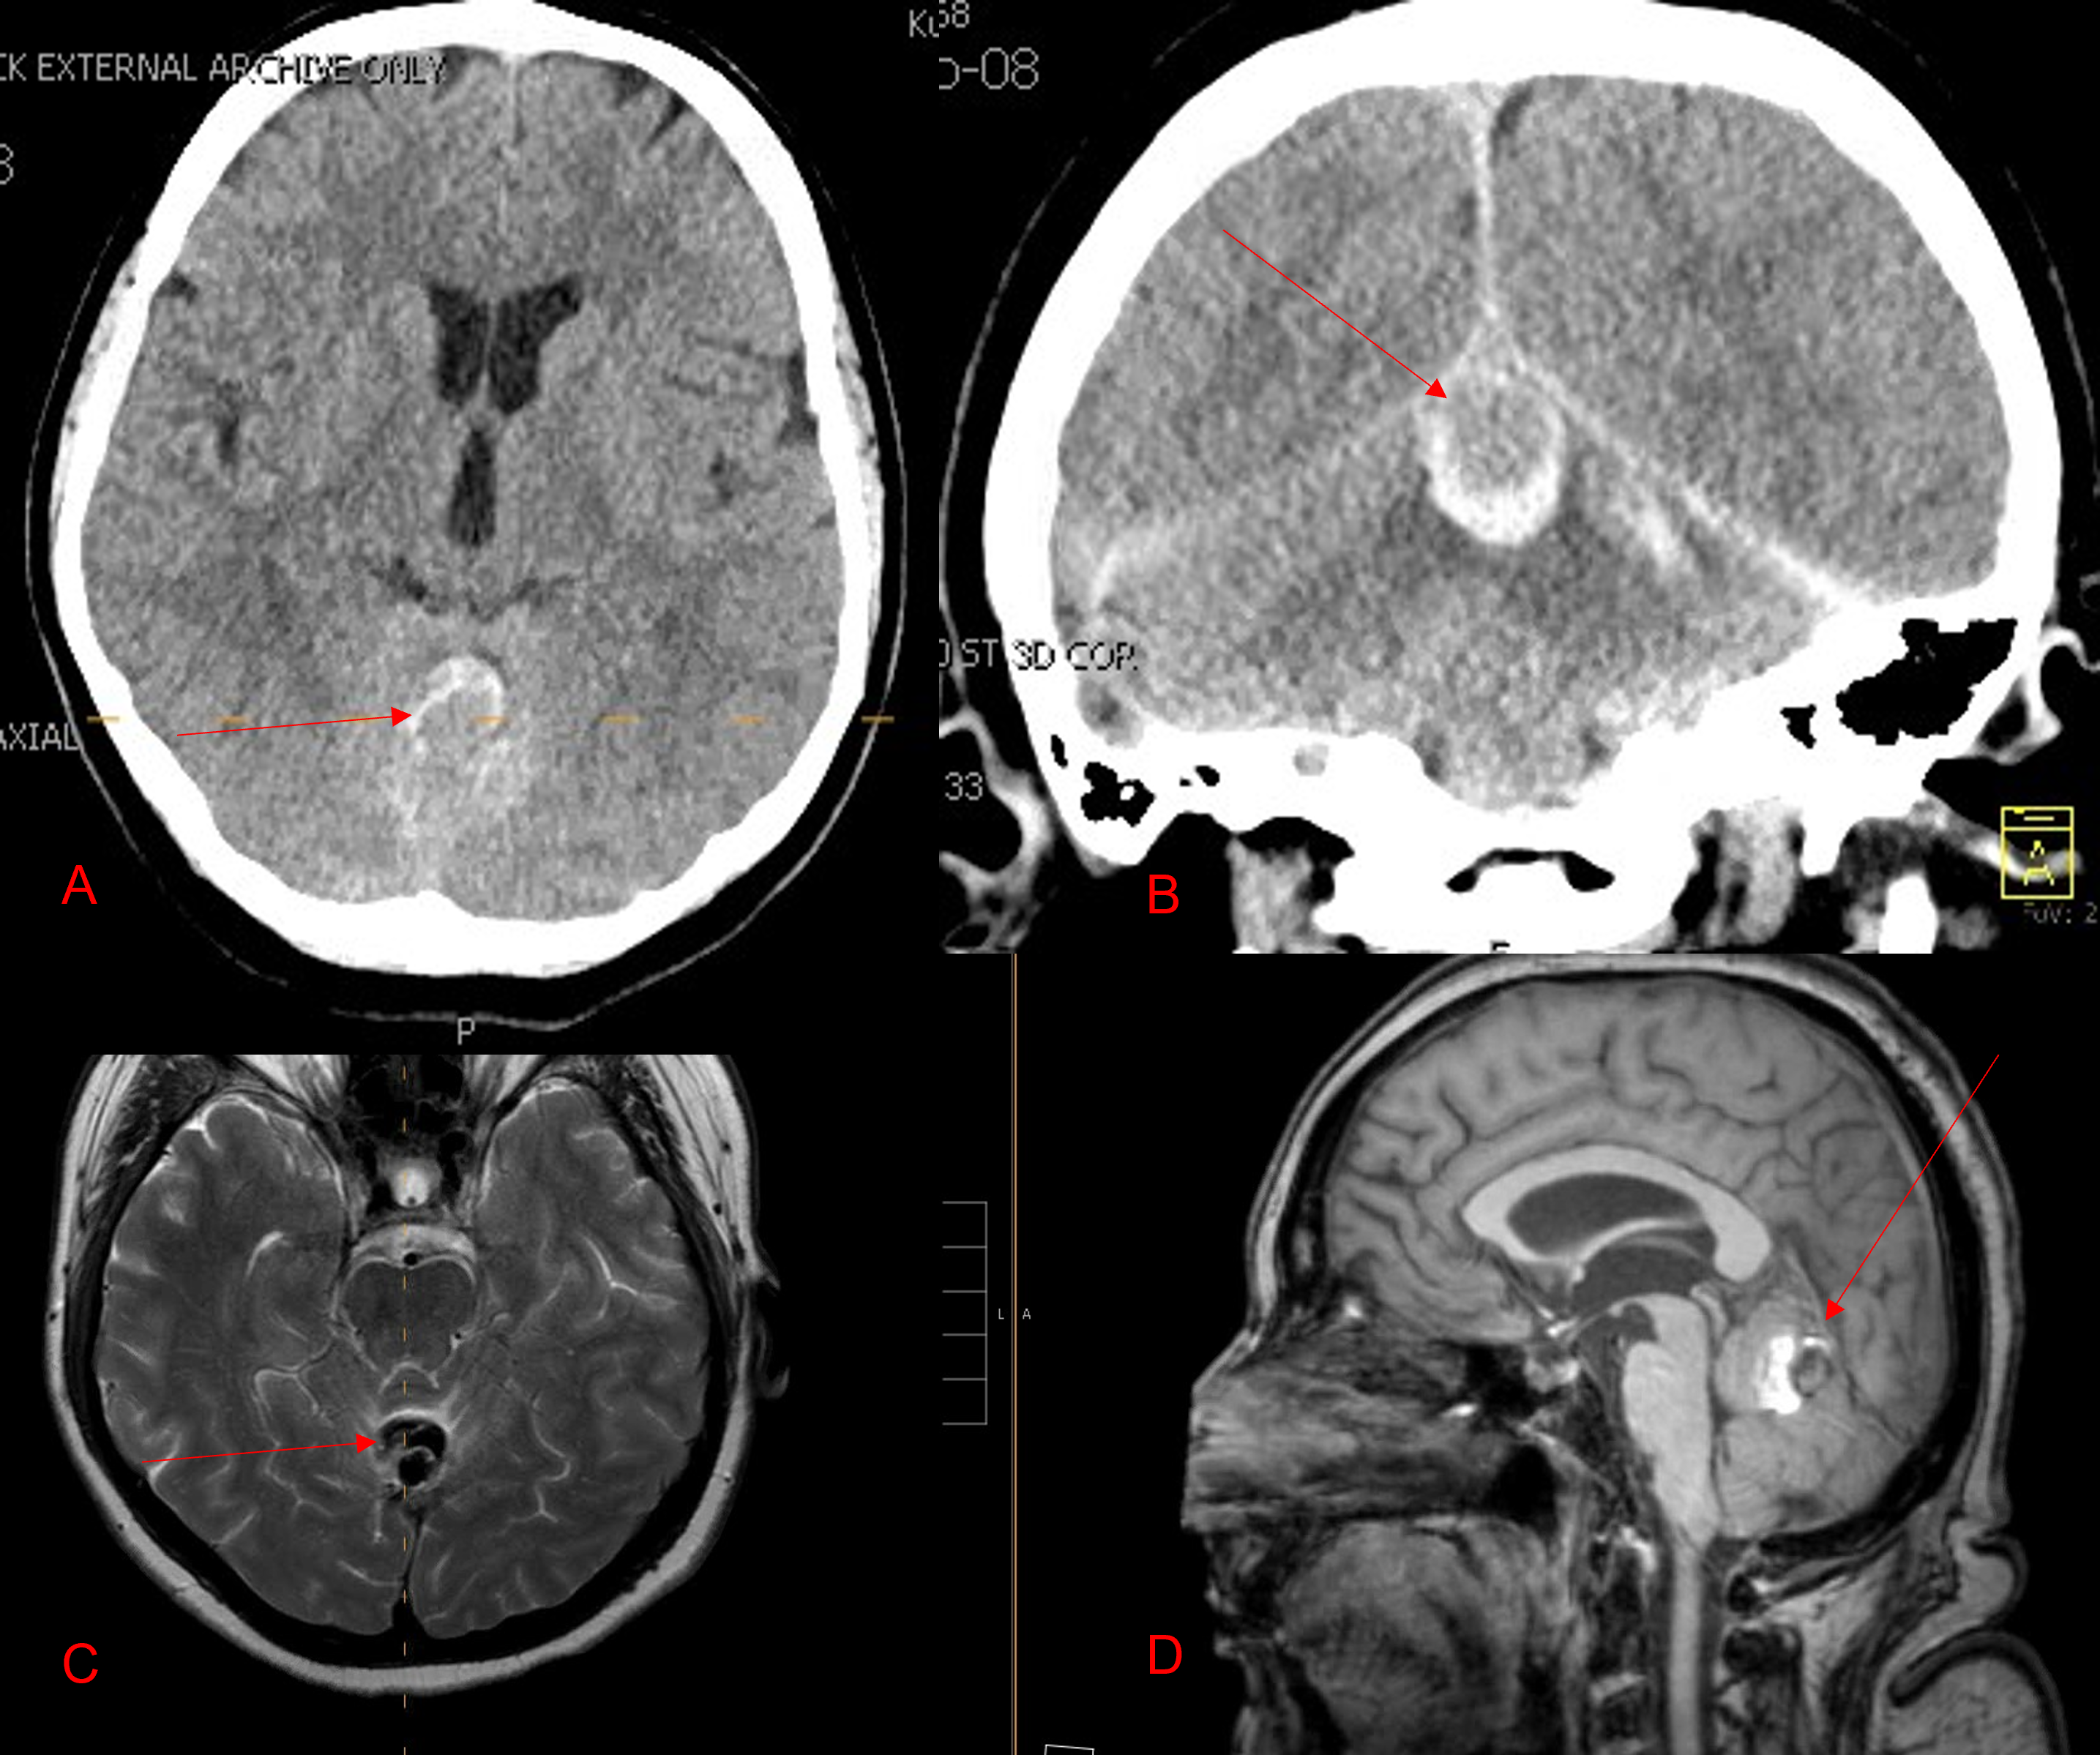

The patient agreed to receive minimally invasive treatment with Bilateral Middle Meningeal Artery Embolization, a new approach to promote resorption of chronic and subacute subdural hematomas in patients that are not improving with conservative measures or have contra-indications to surgical evacuation. Selective catheterization of the Middle Meningeal Artery is followed by transarterial embolization of the territory and inflammatory membranes that are felt to be secreting serosanguinous proteinaceous exceeding the capacity for resorption. MMA embolization was performed bilaterally in this patient. (Figure 2. A and B)

Figure 2. A) Initial right ECA angiogram ; B) Post MMA Embolization; C) Selective Embolization Of Middle Meningeal Artery Membranes using PVA particles (arrows).